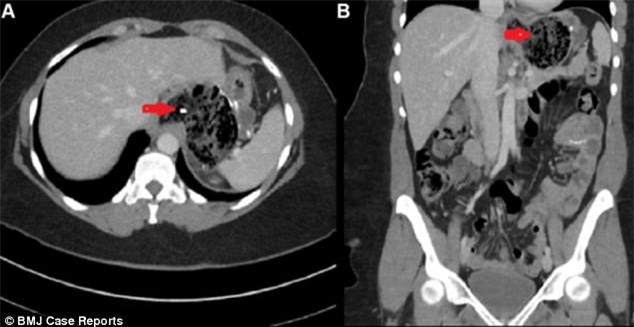

Sau khi tiến hành siêu âm vùng bụng, các bác sĩ đã vô cùng bàng hoàng khi phát hiện ra trong dạ dày của người bệnh là một khối dị vật khổng lồ gồm những tóc và tóc, có cả thức ăn trộn lẫn trong đó.

Qua thăm khám, các bác sĩ đã chẩn đoán, người phụ nữ bị mắc một hội chứng có tên y khoa là Rapunzel, một trong những hội chứng rối loạn tâm lý khiến người mắc phải sẽ có một thói quen khó bỏ, thậm chí có thể coi là nghiện, đó là tự ăn tóc của mình.

Rapunzel là một hội trứng rối loạn tâm lý hiếm gặp, nó khiến người bệnh mắc phải có một thói quen đó là ăn tóc của mình. Tích tụ lâu dài, những sợi tóc ăn vào sẽ không thể tiêu hóa được và tạo thành một khối dị vật. Khi dị vật này càng lớn, chúng sẽ gây ra buồn nôn và đau bụng.